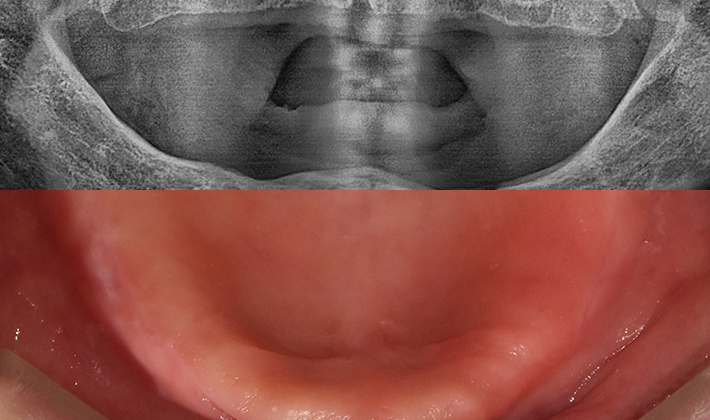

치과가 무서워 10년 동안 미뤄온 임플란트 수술 그 결과는?

2026.01.21